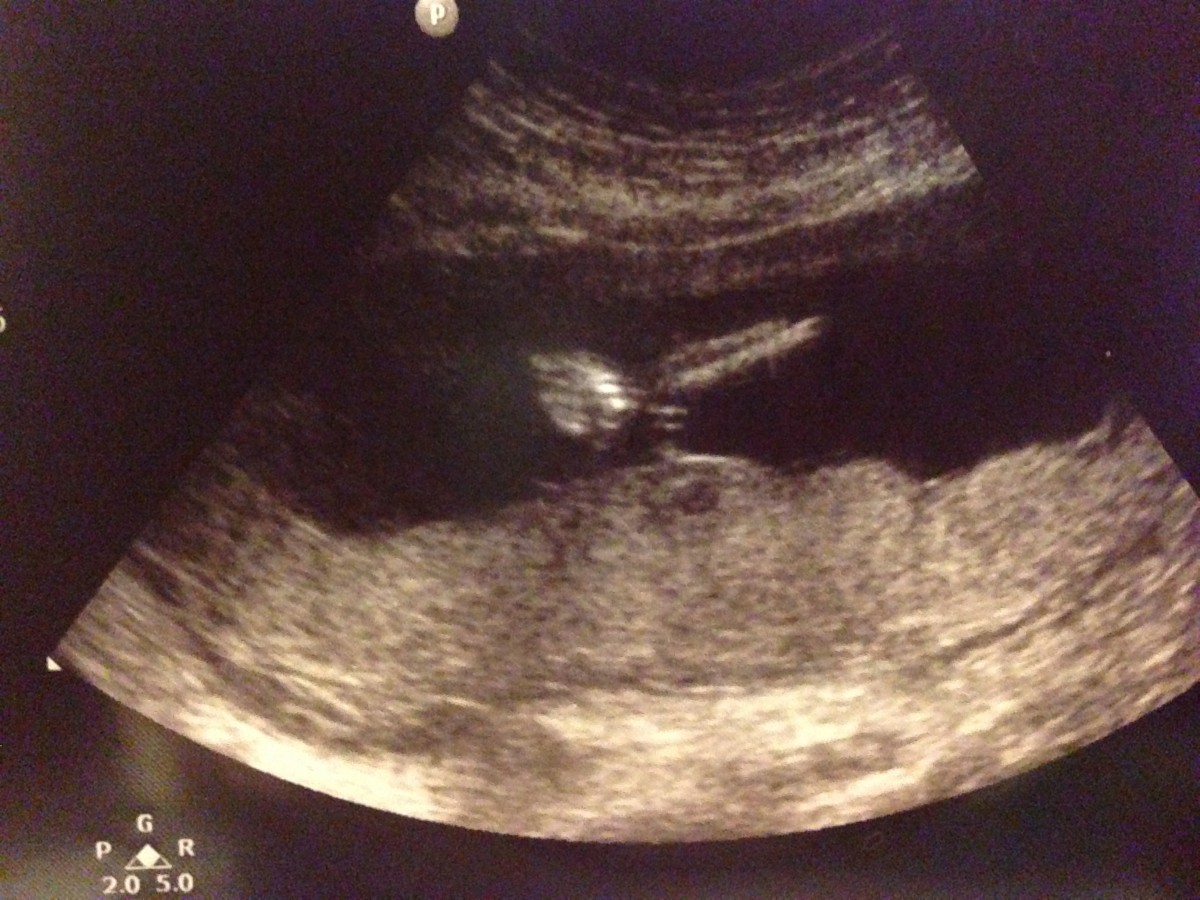

呢張睇到成個頭+身嘅shape清楚啲~:)

除咗望到BB呱高興之外,S醫生都幫我哋睇下現階段望到嘅身體各部份,當然,20週嘅morphology scan(結構超聲波)先至更適合睇detail啦~頭仔入面腦部嘅ventricles啦、paranasal bones啦、心臟同胃bubble相對嘅位置啦、橫隔膜啦、脊椎完整性啦、泌尿系統啦、手手腳腳啦⋯IMG_5194

原來咁細個baby已經睇到個膀胱﹗係呀,佢身邊包圍住佢嘅胎水咪就係自己啲尿尿囉,所以腎臟、膀胱已經開始運作㗎啦~IMG_5195

因為一般超聲波只係唔同角度嘅切面,baby係立體㗎嘛,當然唔可能同一個cut睇到晒全身各部份啦,佢不斷揮動嘅手,好不容易先捕捉到其中一隻影到相﹗:D 14週嗰次睇落瞓緊覺,今次唔似了,因為好活潑丫﹗